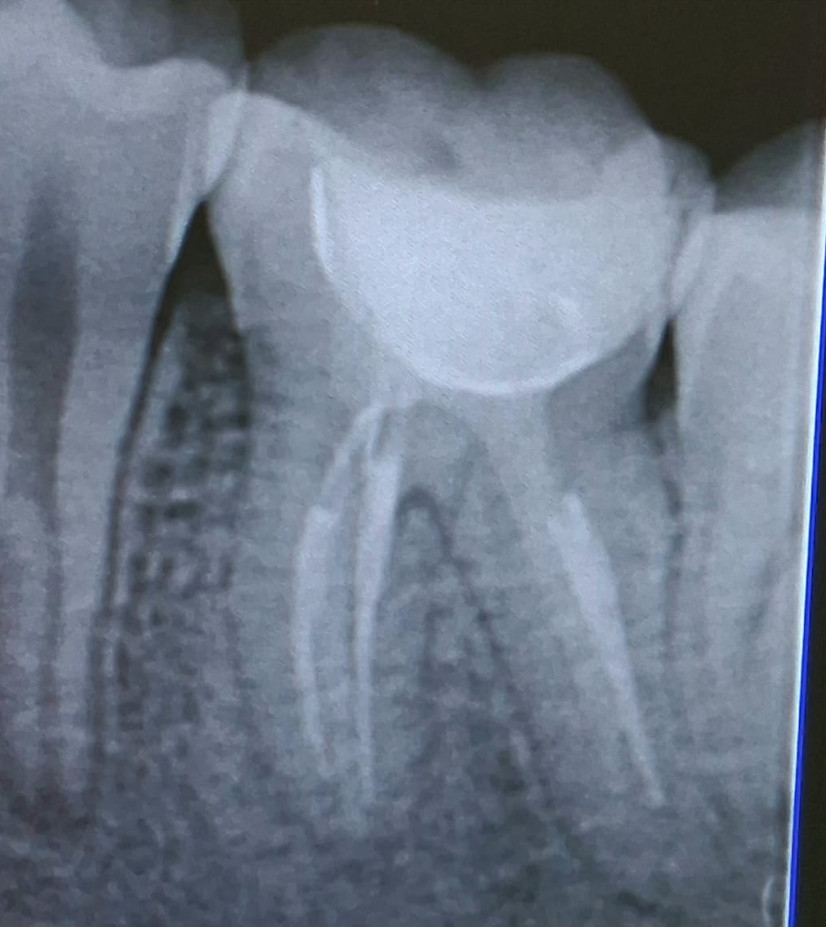

Caso Clinico

Il restauro di un dente cariato o fratturato si ottiene con il composito. È un materiale, in uso

da circa 45 anni, che diviene tutt’uno col dente.

È innocuo al dente e all’organismo. La gran parte dei restauri ha già superato i 35 anni.